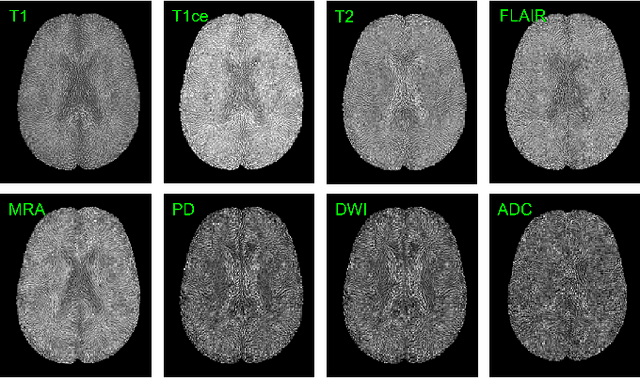

Abstract:Accurate diagnosis of brain abnormalities is greatly enhanced by the inclusion of complementary multi-parametric MRI imaging data. There is significant potential to develop a universal pre-training model that can be quickly adapted for image modalities and various clinical scenarios. However, current models often rely on uni-modal image data, neglecting the cross-modal correlations among different image modalities or struggling to scale up pre-training in the presence of missing modality data. In this paper, we propose BrainMVP, a multi-modal vision pre-training framework for brain image analysis using multi-parametric MRI scans. First, we collect 16,022 brain MRI scans (over 2.4 million images), encompassing eight MRI modalities sourced from a diverse range of centers and devices. Then, a novel pre-training paradigm is proposed for the multi-modal MRI data, addressing the issue of missing modalities and achieving multi-modal information fusion. Cross-modal reconstruction is explored to learn distinctive brain image embeddings and efficient modality fusion capabilities. A modality-wise data distillation module is proposed to extract the essence representation of each MR image modality for both the pre-training and downstream application purposes. Furthermore, we introduce a modality-aware contrastive learning module to enhance the cross-modality association within a study. Extensive experiments on downstream tasks demonstrate superior performance compared to state-of-the-art pre-training methods in the medical domain, with Dice Score improvement of 0.28%-14.47% across six segmentation benchmarks and a consistent accuracy improvement of 0.65%-18.07% in four individual classification tasks.